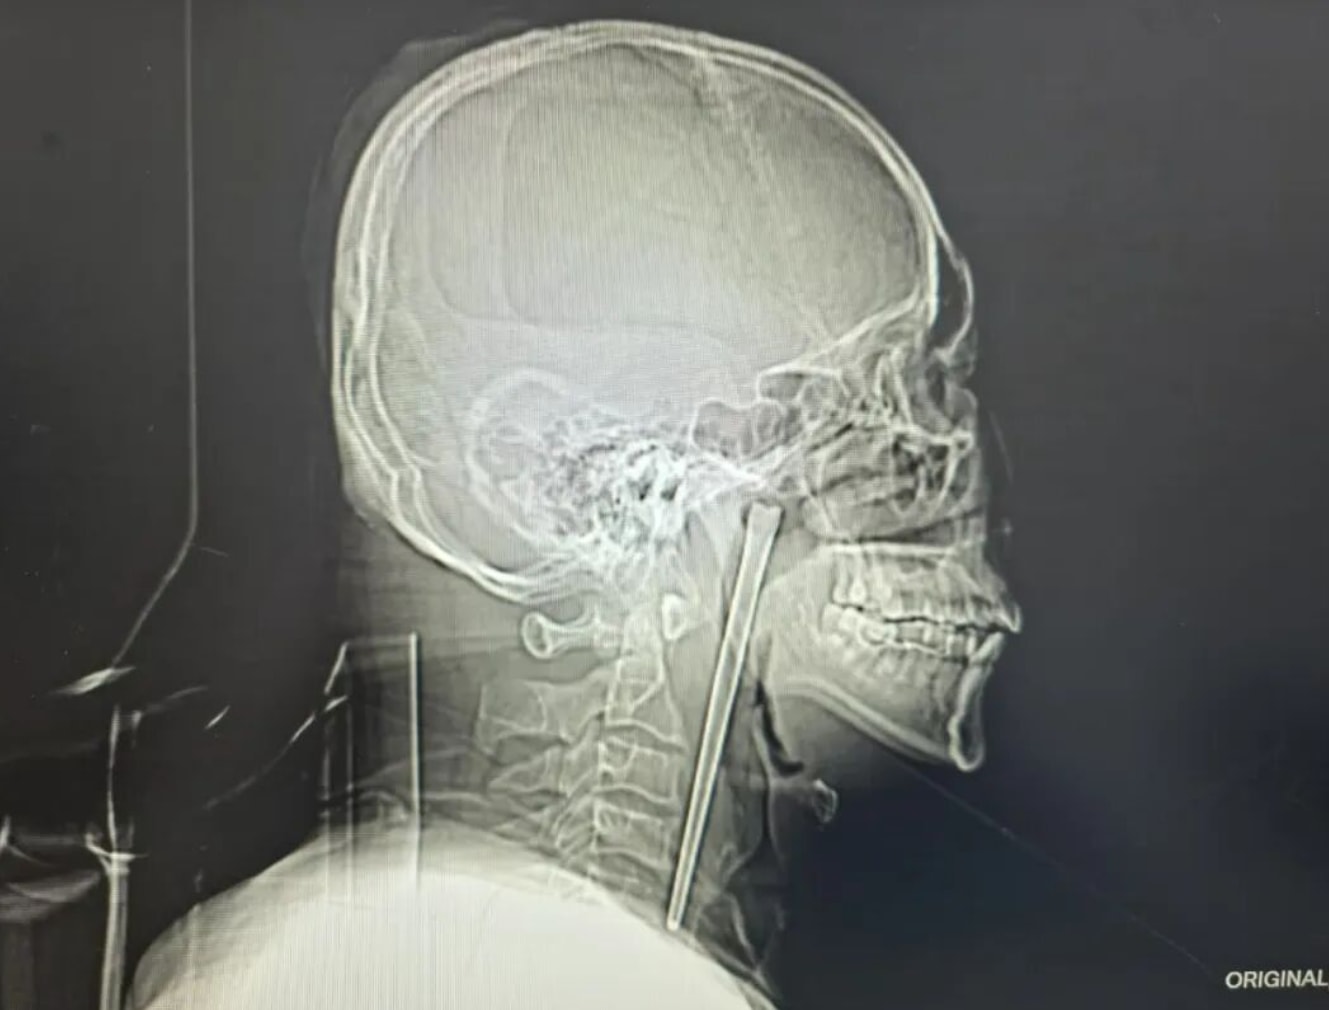

A 46-year-old man in Dalian has left doctors stunned after living with a 12cm metal chopstick lodged in his throat for eight years, with 3cm of it still sticking out the side of his throat.

He rushed to the hospital, where scans revealed the chopstick had been embedded in the upper right side of his throat, behind the soft palate, with about 3cm still sticking out.

Despite everything, doctors found no major damage — no infection, no bleeding, and no structural issues with his vocal cords.

Taking into account his earlier concerns about invasive surgery, doctors opted for a minimally invasive transoral procedure, removing the chopstick through the mouth instead of making an external incision.

The entire 12cm stainless steel chopstick was successfully removed.